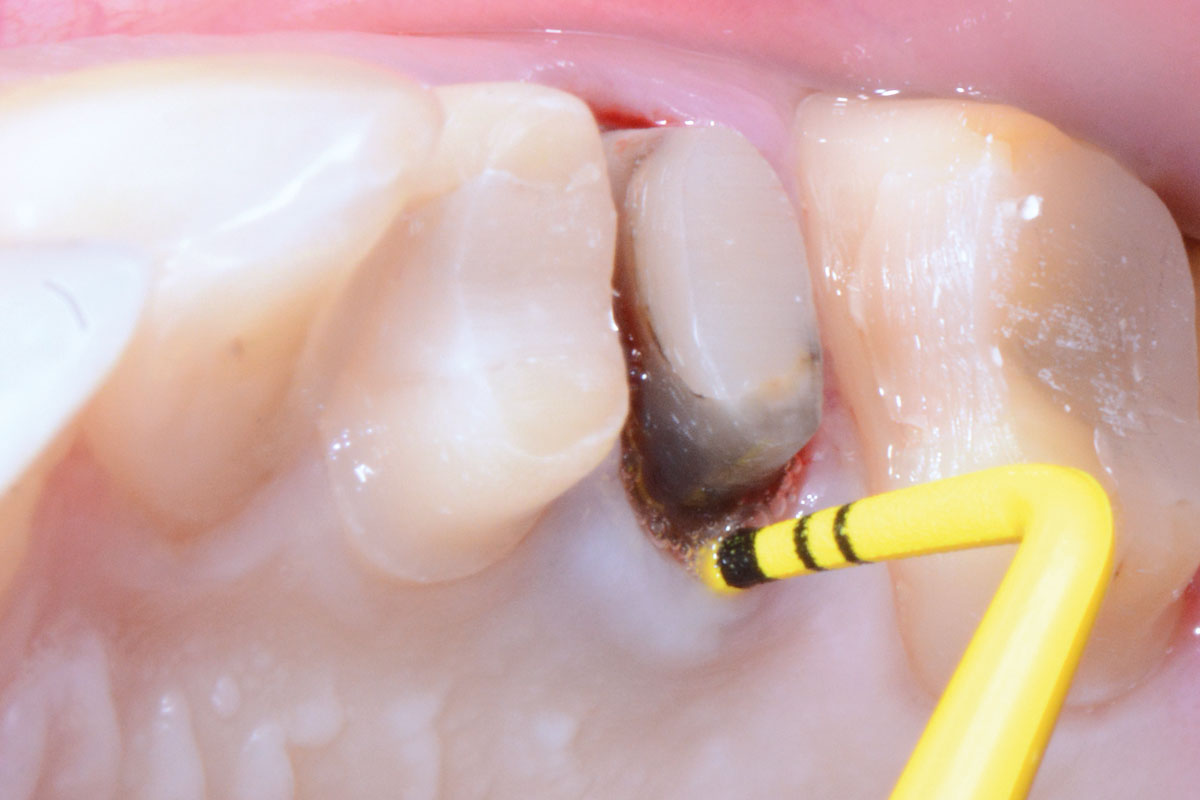

02/16 - Advanced loss of palatal boneFull bone regeneration in extraction socket augmented with maxgraft® and Jason® membrane – Dr. C. Landsberg